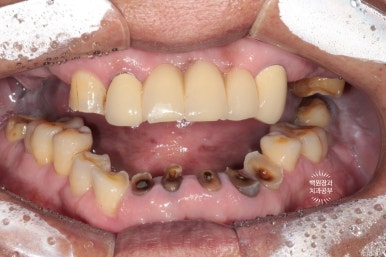

처음 오셨을 때의 상태입니다.

엑스레이를 같이 참고해 보셔야 하는데요,

양쪽 위 큰 어금니가 모두 발치된 상태로 오래 지내신 분이었어요.

보시면 상대적으로 아래 앞니가 머리가 매우 조금만 남아있는 것을 보실 수 있으실텐데요,

아래 앞니가 저렇게까지 극적으로 사라지게 된 경위를 살펴보자니

위 어금니가 없는채로 오래 지내시다보니

주로 앞니로 식사를 하게 됩니다.

위 앞니는 금속-도재 고정성보철물(PFM bridge)로 제작이 되어있는데요, 도재가 씌워진 보철물에 의해 아래 앞니의 마모가 가속화되고

결국 아래 앞니의 머리가 없어질때까지 깨지고 닳고.. 그런 과정을 거치게 된 것이죠.

대구치의 상실은 교합의 붕괴에 가장 큰 영향을 주는 것 같습니다.

아래 앞니의 마모도가 상당히 심합니다.

치과에서 교모(attrition)라고도 하는데요, 머리가 닳아 없어지다보니 치아 내부의 신경관이 드러나게 되고

그렇게 발생한 치통을 해결하기 위해 신경치료를 모두 받으셨던 흔적도 보여요.

여튼.. 심각합니다. 치료가 시급한 상태셨어요.